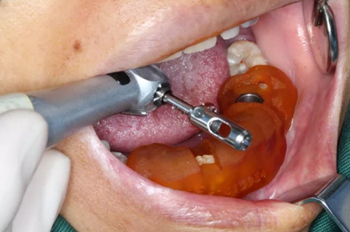

3.根據(jù)手術(shù)計劃書,使用術(shù)前所設(shè)計好的長度、直徑的一系列鉆針在導(dǎo)板的引導(dǎo)下進行備孔。

4.在全程導(dǎo)板的引導(dǎo)下,使用全程導(dǎo)板工具盒中的攜帶器,從導(dǎo)板套環(huán)孔處將植體植入,直至攜帶器的六角、與導(dǎo)板套環(huán)的六角嚴絲合縫(如圖,六角對六角),即表示植體就位成功。